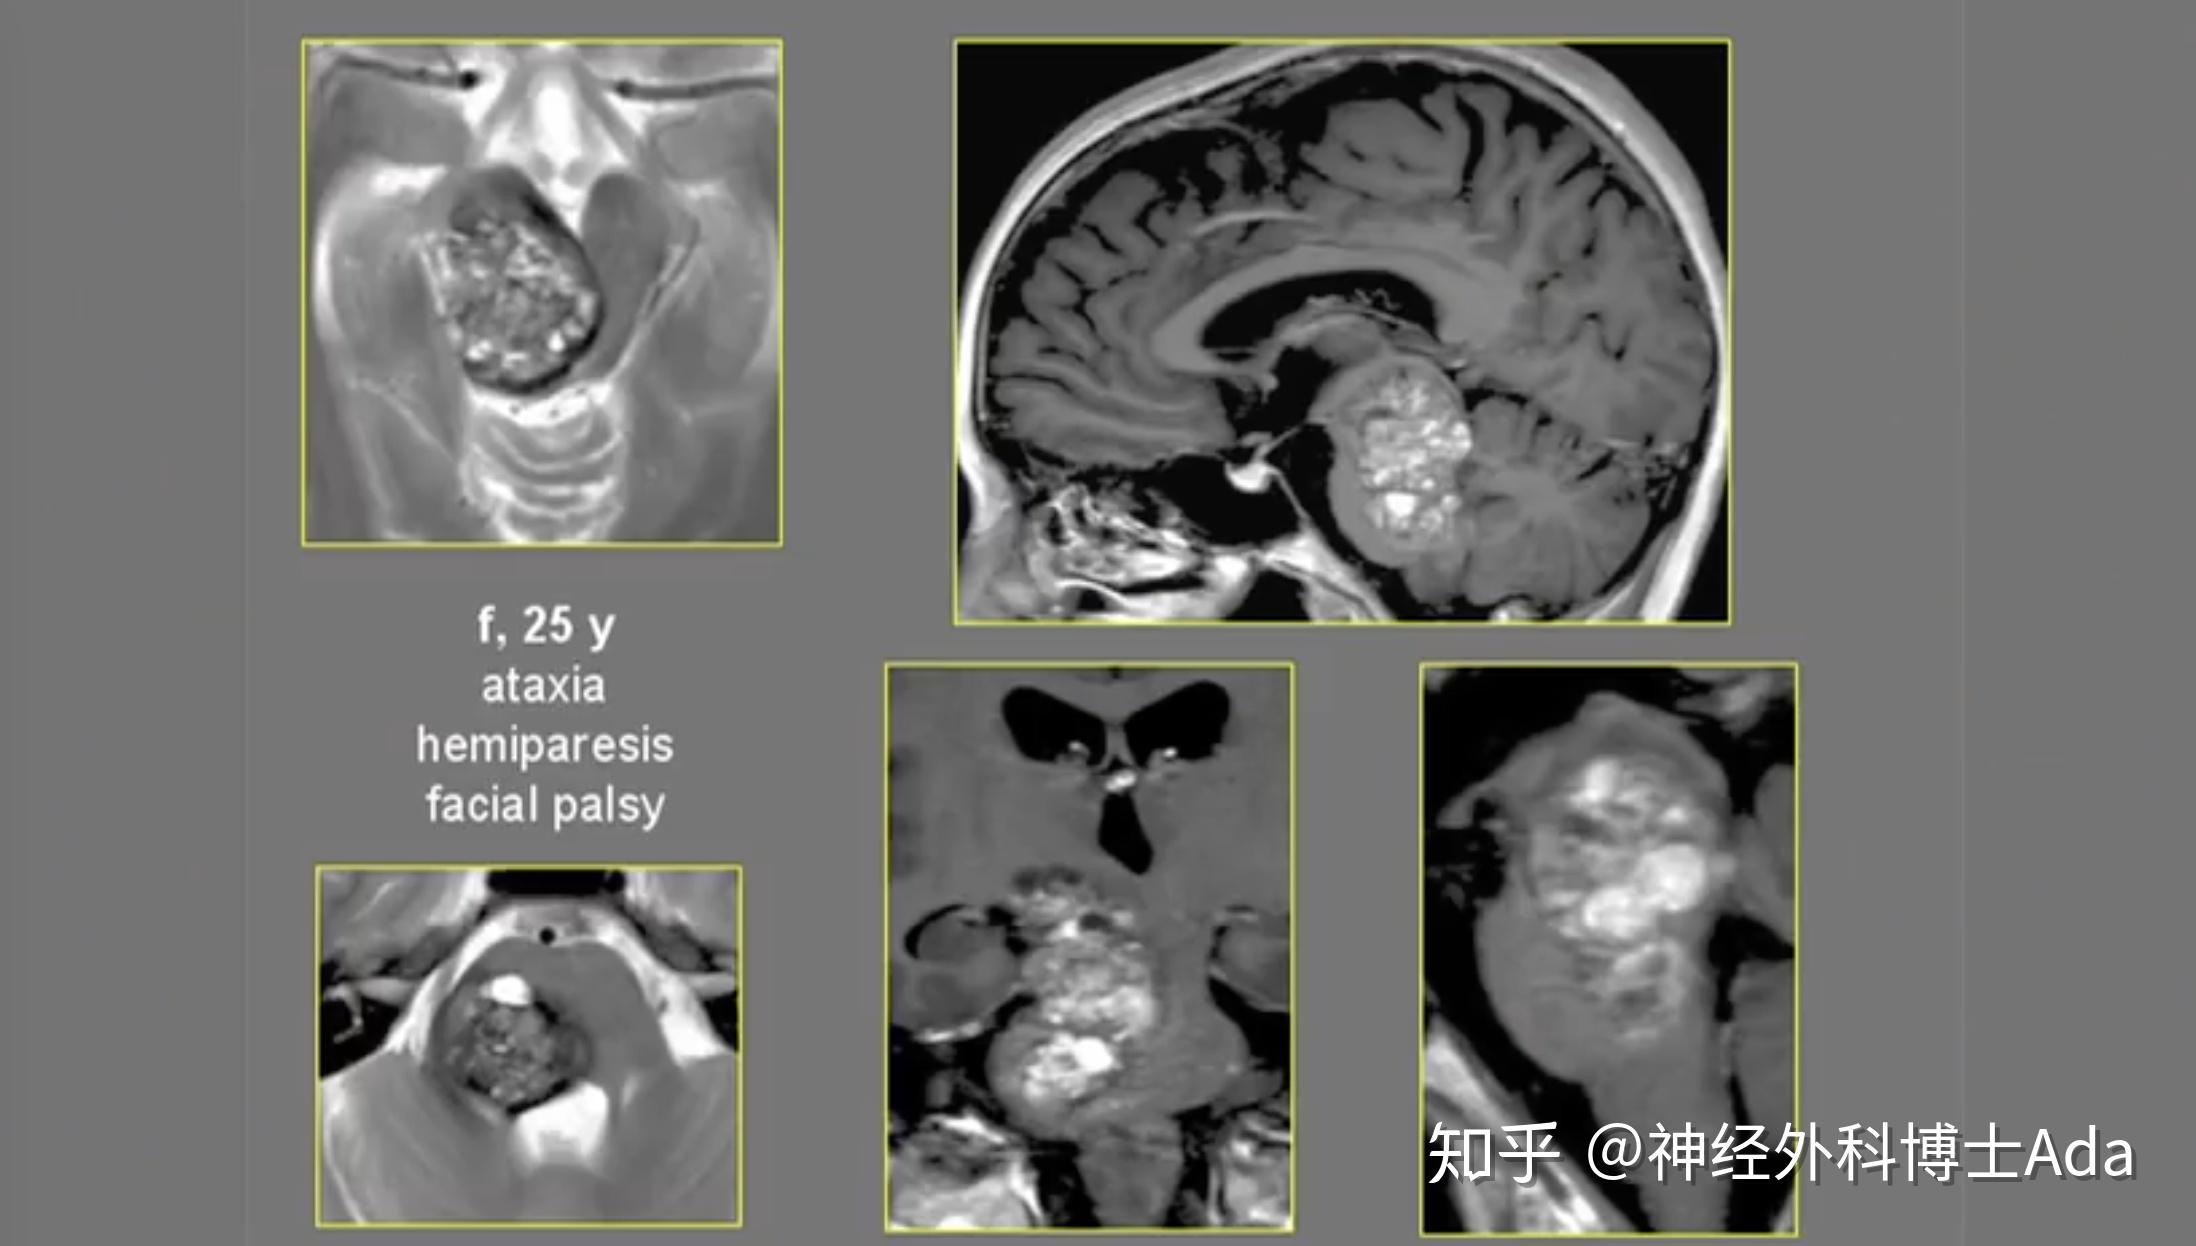

25岁女性巨大脑干海绵状血管瘤全切手术病例

图片尺寸2196x1246